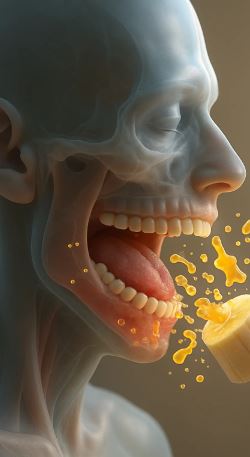

2. Oral Bacteria & Heart Attack / Heart Surgery Failure

“Image shows the failed root canal, with infection still remaning at the base“

How gum bacteria influence the heart:

- Bacteria like P. gingivalis have been found inside heart arteries, inside plaques.

- They weaken plaque walls → making them rupture → forming a clot → heart attack.

- They increase inflammation (CRP, IL-6), which damages arteries.

Why root-canal infections are dangerous in heart patients

Residual bacteria trapped under crowns/root canals can enter blood:

- During chewing

- During brushing

- During surgery

- During dental cleaning

For heart valve patients, this can trigger infective endocarditis, which is often fatal.This is why cardiologists warn patients about dental hygiene before heart surgery.For heart valve patients, this can trigger infective endocarditis, which is often fatal.This is why cardiologists warn patients about dental hygiene before heart surgery.